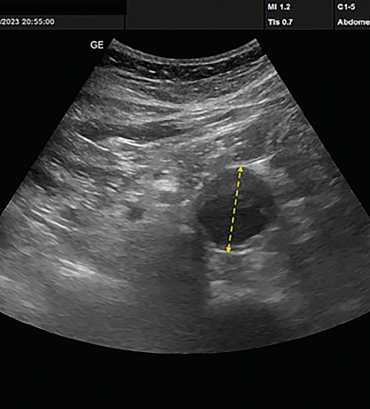

Obr. 1 POCUS nález dilatace břišní aorty (zevní – zevní kontura cévy cca 35 mm) u pacienta z kazuistiky (trvání vyšetření 4 min) POCUS – Point‑of‑Care ultrasonografiePro přítomnost varujícího příznaku pokládáme cílenou klinickou otázku na patologii břišní aorty. Provedené POCUS vyšetření břišní aorty v nejširším místě s nálezem dilatace kontury cévy 35 mm (měření zevní – zevní kontury cévy na dlouhou osu aneuryzmatu). Ilické tepny nebyly zobrazovány (obr. 1). Na základě provedených vyšetření byla stanovena pracovní diagnóza aneuryzmatu břišní aorty a pacient byl týž den odeslán, pro regionální nedostupnost kardiovaskulárního centra, k akutnímu cévnímu vyšetření k dalšímu došetření. Všechna uvedená vyšetření byla provedena v ordinaci všeobecného praktického lékaře během 20 minut. Regionálně běžná objednací doba pro tradiční ultrazvukové vyšetření břicha byla v daném období v rozmezí 4–6 týdnů, objednací doba cévního vyšetření 6–7 měsíců.